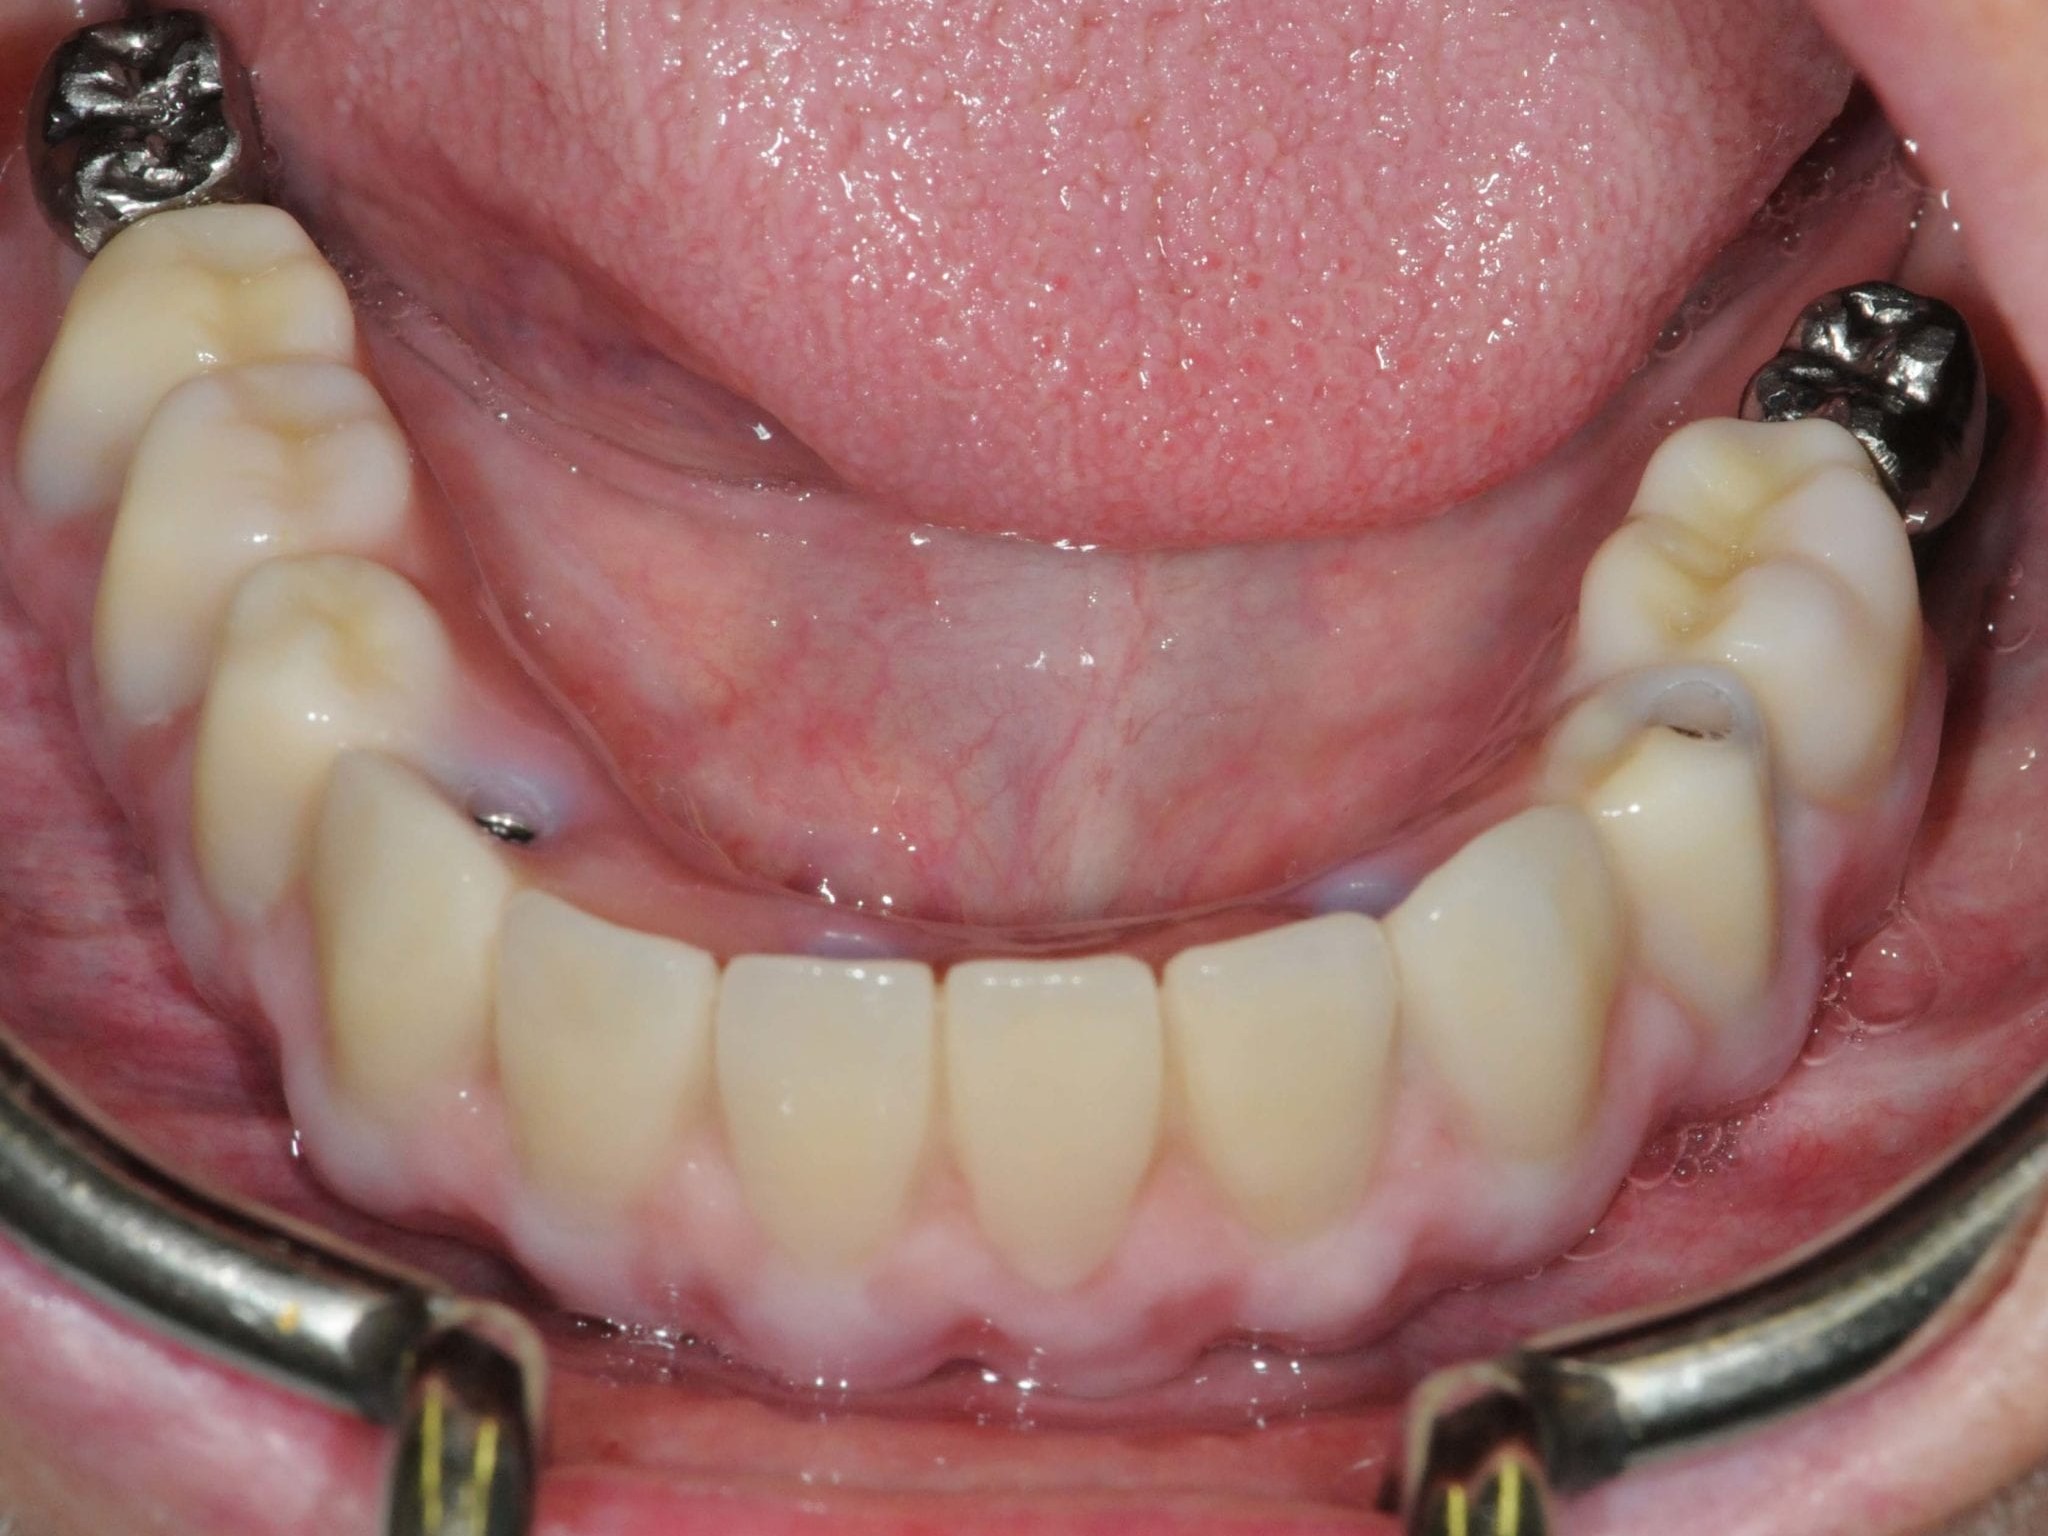

Bei dem nachfolgenden Fall handelt es sich um eine 73-jährige Nichtraucherin im guten allgemeinen Gesundheits- und Ernährungszustand. Die Patientin steht in keiner medikamentösen Behandlung und wies keine Allergien auf. Die Patientin kam 2012 zu uns in die Behandlung. Damals zeigte sich bei ihr eine festsitzende aber insuffiziente Rehabilitation im Unterkiefer, wobei die beiden Blattimplantate die gesamte Rekonstruktion trugen. Die Unterkieferzähne, die bisher die anteriore Abstützung bildeten, waren unter der prothetischen Versorgung kariös zerstört (Abb. 1). Seitens der Patientin bestand der Wunsch nach hochwertiger Rehabilitation des Unterkiefers möglichst mit einer Sofortversorgung. Eine zwischenzeitliche Versorgung mit einer schleimhautgetragenen Interimsprothese schied aus. Darüber hinaus war für die Patientin wichtig, eine möglichst geringe Belastung durch die anstehende Behandlung zu erfahren. Der Oberkiefer war mit eine herausnehmbaren Vollprothese rehabilitiert. Zur exakten Vorhersagbarkeit der Implantatpositionen wurde ein DVT angefertigt. Im Anschluss erfolgte eine gemeinsame Planung der chirurgischen sowie prothetischen Implantatposition im Team, bei der Chirurg, Prothetiker und Zahntechniker im ständigen Dialog standen (Abb. 2 und 3).

Für die Allgemeinanästhesie erfolgte zunächst die zusätzliche Gabe eines typischen Infiltrationsanästhetikums. Intravenös wurde unmittelbar präoperativ das Antibiotikum Clindamycin 600 mg gegeben. Abbildung 7 zeigt die klinische Ausgangssituation linksseitig. Nach der vorsichtigen Durchtrennung der Brückenkonstruktion (Abb. 8) jeweils vor der Krone auf den Blattimplantaten und Entfernung der nicht erhaltungswürdigen Zähne 44 bis 33 samt ihrer Überkronung (Abb. 9) wurde der Mukoperiostlappen vestibulär wie lingual passend zur erstellten Schablone präpariert und die Bohrschablone in ihrer finalen Lage eingebracht (Abb. 10). Zunächst erfolgte die Insertion der angulierten Implantate Ankylos ® C/X-Implantate (Durchmesser 3,5 mm) der Länge 14 mm in regio 034 (Abb. 11 und 12) und 044. Danach wurden in den Positionen 032 und 042 jeweils ein weiteres Ankylos ® C/X –A-Implantat mit gleicher Länge und Durchmesser inseriert (Abb. 13). Sämtliche entfernten Knochenpartikel und auch Bohrspäne wurden akribisch asserviert. In den Positionen 032 und 042 wurden Ankylos ® Balance Basisaufbauten C/ (GH 3,0 / Ø 5,5 mm, Kopfhöhe 2,4 mm) mit 15 N/cm eingeschraubt. Anschließend hat der Zahntechniker mittels der Ankylos ® Modellierhilfskappenfür den Balance Basisaufbau Retentionskappen hergestellt, die mit 25 N/cm eingebracht wurden (Abb. 14). Am Implantat regio 042 wurde der Knochen in Schalentechnik nach vestibulär aufgebaut (Abb. 15)⁹,¹⁰. Im nächsten Schritt haben wir die angulierten Ankylos ® Balance Basisaufbauten C (nicht indexierte Abutments) in Regio 034 und 044 (GH 3,0, A30 / Ø 4,2 mm, Kopfhöhe 1,3 mm) ausgerichtet und ihren spezifischen Vorgaben entsprechend eingebracht (Abb. 16). Nachdem sich alle erforderlichen prothetischen Implantatbauteile in situ befanden (Abb. 17), erfolgte die Überprüfung und geringfügige Anpassung des im Vorfeld digital erstellten Sofortprovisoriums. Im Anschluss wurden die leeren Alveolen und Knochendefekte mit dem gewonnenen autologen partikulären Material aufgefüllt. Dann erfolgte der typische Naht-Wund-Verschluss mit Einzelknopfnähten eines resorbierbaren Nahtmaterials (Abb. 18). Nachdem die Patientin aus der Vollnarkose erwacht war und ihre motorischen Fähigkeiten wiedererlangt hatte, wurde das Sofortprovisorium eingesetzt und in Okklusion gebracht. In dieser Position wurden die Retentionskappen über ein selbsthärtendes fluoreszierendes kaltpolymerisierendes Paste-Kartuschensystem fixiert. Anschließend erfolgte die extraorale Versäuberung des Interimszahnersatzes. Nach Refixierung des Sofortprovisoriums in der Mundhöhle (Abb. 19 und 20) und dem Verschluss der Schraubenkanäle mit Kunststoff erfolgte die radiologische Kontrolluntersuchung (Abb. 21).